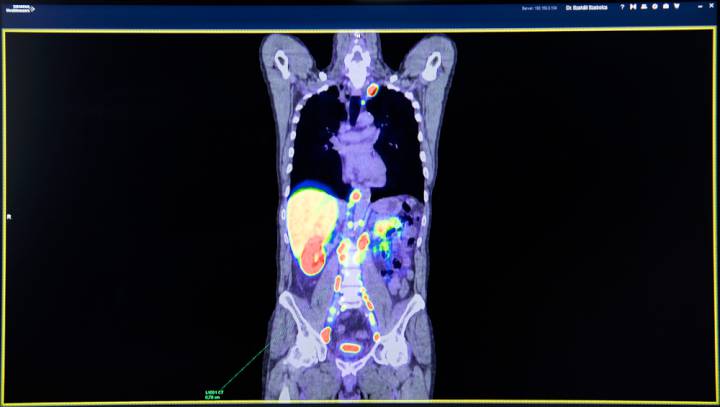

Dr. Szakáll Szabolcs nukleáris medicina szakorvos, a Pozitron-Diagnosztika Központ orvos igazgatója az eljárás lényegét ismertetve elmondta: a statisztikák szerint a prosztatarák Magyarországon a férfiak második leggyakrabban diagnosztizált daganata, mely az ötödik vezető halálok, az öregedő európai társadalmakra általában jellemzően. Évente öt-hatezer új prosztatarákos megbetegedést diagnosztizálnak, a radikális műtéten átesettek egyharmadánál azonban a sebészi- vagy sugárterápiát követően kiújul a betegség. Ennek első jele a PSA-szint emelkedése, ez pedig fel nem fedezett áttétek jelenlétével magyarázható. A laborvizsgálattal megállapított PSA-szint azonban nem nyújt információt az áttétek helyéről – hangsúlyozta Szakáll doktor hozzátéve: a vizsgálat egy, a prosztatarák-sejteken akár több százszorosan előforduló fehérje – a prosztata specifikus membránantigén (PSMA) – kimutatásán alapul. Az ehhez kötődő PET-nyomjelzők eddig soha nem látott kontraszttal képesek kimutatni a prosztatarákot. A PSMA PET/CT-vizsgálatok elsődleges célja az ilyen kiújulások felderítése, kimutatása. A vizsgálat – bizonyos feltételek mellett – segítséget adhat a megfelelő kezelési stratégia meghatározásában, a már igazolt prosztatadaganat kezelés előtti stádiumfelmérésével – mondta a nukleáris medicina szakorvos kiemelve: Magyarországon jelenleg az egyetlen PSMA-specifikus, humán célra alkalmazható PET-nyomjelző a Pozitron-Diagnosztika Központban érhető el Budapesten.

Dr. Ágoston Péter sugárterapeuta és klinikai onkológus, az Országos Onkológiai Intézet Sugárterápiás Központjának főorvosa hangsúlyozta, hogy a prosztatarák diagnosztikájában ma a PSMA PET/CT az egyik leghatékonyabb és legérzékenyebb vizsgálat. A nemzetközi szakmai irányelvek szerint a prosztatarákos betegeknél két területen alkalmazható. A prosztatadaganat elsődleges kezelését, radikális műtétjét vagy sugárkezelését követően a daganat kiújulását a vizsgálómódszerek között a legkorábban jelzi. Már 0,3-0,5 ng/ml-es prosztata specifikus antigén (úgynevezett PSA) emelkedéskor (ez jelzi a betegség állapotát, kiújulását) 80%-ban képes kimutatni a kiújuló daganat helyét, nagyban segítve ezzel a kezelést. Másik javasolt terület a nagyobb kockázatú, rossz kórjóslatú, frissen felfedezett prosztatarák esetén a betegség kiterjedésének, stádiumának meghatározása. Ilyenkor a PSMA PET/CT a legpontosabb és legérzékenyebb vizsgálat, ráadásul egy vizsgálattal az egész testről ad információt, nem szükséges többszörös CT, MRI, csont-scan elvégzése. A vizsgálatot ma már Európában nagy számban végzik Németországban, Ausztriában és Olaszországban. A módszer, az eddigi tudományos eredmények alapján, a fenti területeken maga mögé utasít minden korábban erre a célra használt orvosi képalkotó eljárást – szögezte le.